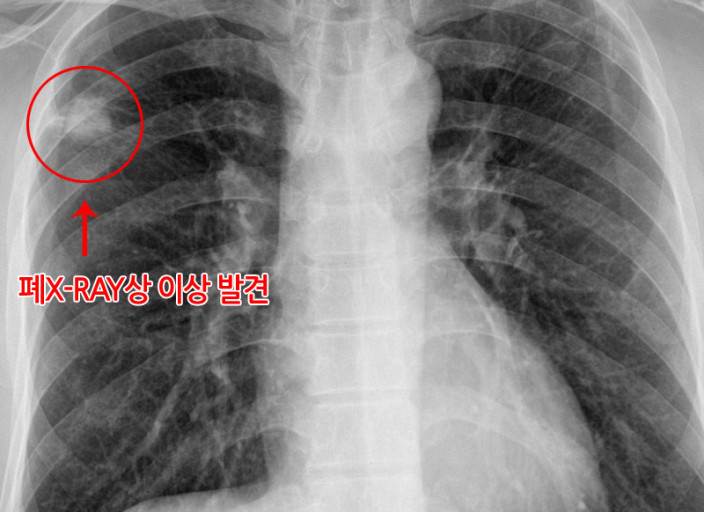

폐암은 위암, 갑상선암 다음으로 3번째로 발병 빈도가 높은 3대 암 중 한 가지인데요. 폐암은 재발과 전이까지의 빈도도 잦은지라 완치가 어렵다고 하며 폐암 발병 초기에는 거의 증상이 없을 수가 있어 수술이 불가능한 3기, 혹은 4기에 주로 진단된다고 해요.

폐암 초기 증상으로 호흡곤란 증상이 있어요. 폐에 문제가 생기니 당연히 숨이 찰 수밖에 없어요. 평상시 조금만 걸어도 숨이 아주 차거나 심하게 가빠지는 등의 호흡에 문제가 발생하게 돼요. 폐에 암세포가 커지기 시작하게 되면 폐허탈, 흉막삼출 등의 질환으로 인해 극심한 호흡곤란을 느끼기도 해요.

폐암 초기증상 다음은 기침인데요. 이것은 호흡곤란과 이어지는 증상입니다. 기침은 가장 흔하게 발생하는 폐암 초기증상인데요. 기침 사실 감기나 천식, 최근에는 코로나 증상 등의 다른 호흡기 질병에서도 흔히 발생하는 증상이라 처음에는 대수롭지 않게 여기고 넘어가는 그럴 경우가 많아요. 하지만 계속해서 기침 증상이 끊이지 않는다면 폐암 체크를 받아보는 게 좋아요.